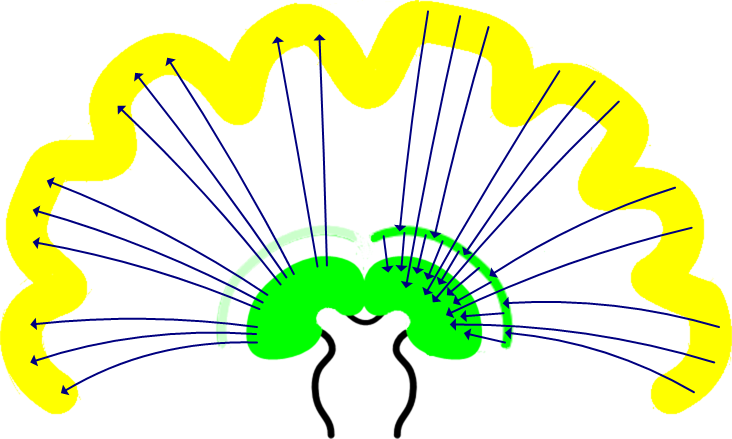

Zoals die kernen in de hersenstam (vermoedelijk) gebruik maken van het neurale netwerk van de reticuliere formatie, maakt de thalamus (vermoedelijk) ook gebruik van een neuraal netwerk. En omdat de thalamus de eerste kern buiten de "buis" van de hersenstam is, kan dat neurale netwerk ook buiten die buis - dat is natuurlijk de cortex die eromheen ligt. De volgende illustratie toont schematisch de verbindingen tussen de twee:

De werking van dopamine is bekend genoeg: het zorgt voor aantrekking tot en met extase, en wel in die mate dat het de feitelijke bron is van alle vormen van verslaving - inclusief zaken als roken en winkelen. En de vele foute oftewel verslavende gedachten.